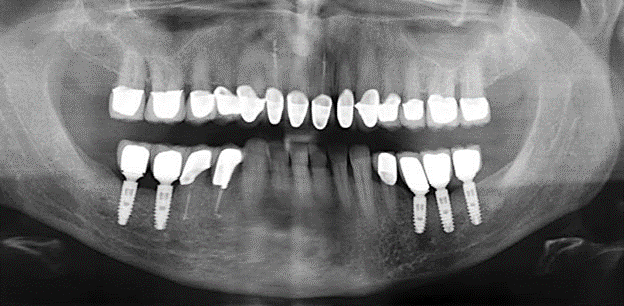

Due to the presence of periodontal disease, SPT was performed every three months in the first years following the insertion. The patient demonstrated a high degree of motivation and good compliance. The pocket depths recorded annually revealed a stable periodontal situation with a BOP index of below five per cent. On the basis of the stable periodontal situation and good cooperation on the patient’s part, the recall interval was extended to every six months as of the sixth year of the prosthetic function phase. Following the change in the recall interval, the respective annual documentation of the periodontal status continued to reveal a stable periodontal situation with no increase in the pocket depths and a BOP index below five per cent (Fig. 2a and b).

The ten-year check-up revealed no indications of advancing clinical attachment loss or peri-implant bone substance loss (Fig. 3).

Fig. 2: The pocket depths recorded annually with six-monthly SPT display no increasing trend and a BOP index of below 5 per cent with a largely inflammation-free periodontal situation. a) PERIO status in 2011 (after five years with implants). b) PERIO status in 2016 (after ten years with implants).

Standardised and regular risk-adapted care in the scope of SPT is the key to treatment success for the clinical long-term success in periodontically compromised patients. This is particularly true for patients fitted with implants following successfully completed periodontal treatment (Fig. 11a and b).